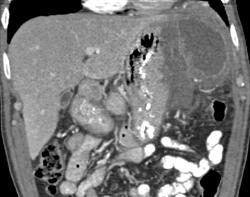

Gastric Banding Procedure With Inflatable Band